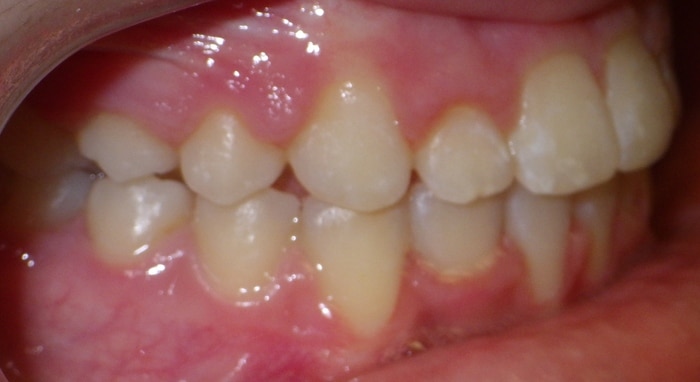

EMILY’S SMILE JOURNEY

Emily began with us as a Phase I patient and we just recently debanded her from Phase II. These progression photos show you that starting early allows us to not just straighten the teeth, but also change the patient’s jaw shape. Emily was a dedicated patient and did great with treatment. Her results speak volumes! We were able to correct her severe underbite and Class III skeletal imbalance without needing jaw surgery.